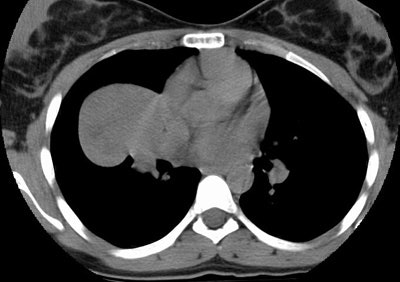

Sclerosing hemangioma:

The images demonstrate an enhancing soft tissue mass within the right lung. The mass has areas of slightly decreased attenuation best appreciated following IV contrast administration. (Click images to enlarge)

Non-contrast CT: